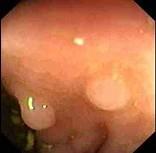

男性,46岁,有结肠癌家族史,行肠镜检查如图,诊断为 ( )A、直肠绒毛样息肉B、克罗恩病C、直肠炎性息肉D、直肠腺瘤样息肉E、直肠癌

问题 男性,46岁,有结肠癌家族史,行肠镜检查如图,诊断为 ( )

选项 A、直肠绒毛样息肉 B、克罗恩病 C、直肠炎性息肉 D、直肠腺瘤样息肉 E、直肠癌

答案 C